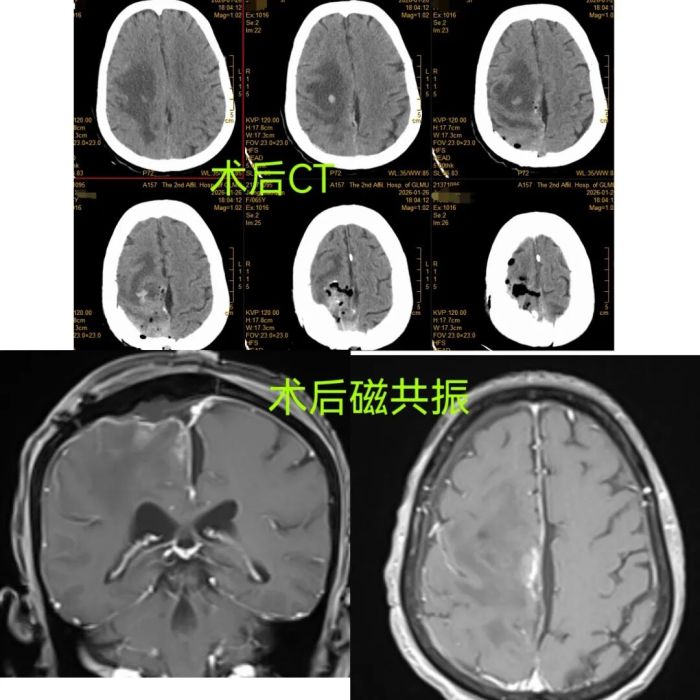

术后CT及磁共振复查结果显示,肿瘤已完全切除。

在全麻下,由经验丰富的手术团队精细操作,凭借娴熟的显微神经外科技术,精准分离、完整切除巨大脑膜瘤,手术过程顺利。术后,医护团队全程严密监护、精心康复指导,患者恢复超出预期:左侧肢体肌力较术前显著改善,术后3天便可下床活动,术后5天可在扶持下独立行走,术后1周顺利康复出院。